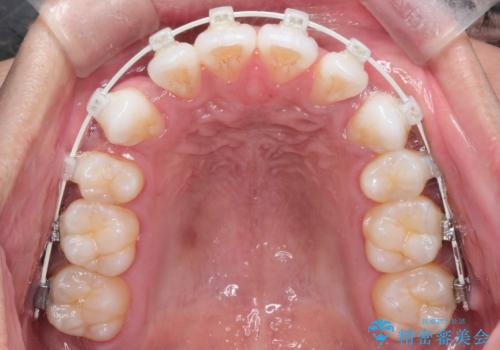

非抜歯で無理に並べようとすると、歯列が外側に広がり、前歯が前方に突き出て口元が突出してしまうリスクがありました。患者様の「これ以上前歯を外に出したくない」という強いご希望を重視し、上下左右の4番目の歯(第一小臼歯)を計4本抜歯してスペースを確保する計画を立案。装置は、装置の見た目を考慮し、白く目立ちにくい審美ワイヤーを選択しました。

抜歯によって作られたスペースを利用し、前歯を後方に維持したまま、ガタついている歯を一つひとつ正しい位置へと整列させていきました。

審美ワイヤーを用いることで、歯の根元から角度を精密にコントロールし、前歯が前方に傾斜するのを防ぎながらスペースを閉じていきました。これにより、口元のボリュームを維持したまま、美しいアーチ状の歯並びを構築することが可能となりました。